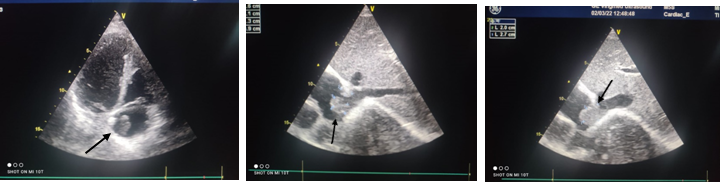

Exo-KQ –da: sağ atriumda inferior vena cavanın sağ atriuma açılan yerində 27x20 mm ölçüdə tromb izləndi (şəkil 1).

15 gün sonra təkrar Exo-KQ müayinəsində sağ atriumda tromb izlənmədi.